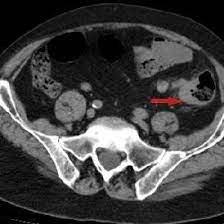

Can Cat Scan Find Colon Cancer - Scielo Brasil Differentiation Between Stercoral Perforation And Colorectal Cancer Perforation Differentiation Between Stercoral Perforation And Colorectal Cancer Perforation / Often the doctor will recommend a ct scan for a detailed examination of internal organs such as the large.. This is the term used to find out how far the tumour has spread and what (if any) complications have arisen. Computed tomography (ct or cat) scan. Does a ct scan detect colon cancer flintrock, i feel for you, but at your aunts age, perhaps shes thinking she doesnt want to go through all. A ct scan may see irregularities in the liver that may be malignant. Routine colonoscopies can find colon cancer in its early stages.

The images often help doctors find out if they can remove the tumor through surgery or if it has metastasized (spread to. Can ct scan detect colon cancer? Because colorectal cancer often bleeds into the large intestine or rectum, people with the disease may become anemic. Preparation before test lab ct scan procedures. It occurs both in men and in women.

Can ct scan detect colon cancer? Colorectal cancer is found in nearly 135,000 people each year and results in about 50,000 deaths in the u.s. What happens before the cat scan? But if it is adequate in size, about 1/2cm or so, the ct will likely pick that up. Ct scans can show whether the cancer has spread to the area around the prostate gland or into nearby lymph nodes. A ct scan may see irregularities in the liver that may be malignant. Colon cancer develops when tumorous growths develop in the large intestine. Ct scans help doctors diagnose and treat medical conditions such as pancreatic cancer. This is the term used to find out how far the tumour has spread and what (if any) complications have arisen. It occurs both in men and in women. Cancer of the pancreas is rarely diagnosed until it is in the final stages, which is why yes, it can. Metastatic colon cancer can be treated with chemotherapy, which is known to be the standard treatment for metastatic colon cancer, apart from chemotherapy, treatments like radiation therapy and targeted therapy can also be. Find out about symptoms and risk factors for colon cancer, also called colorectal cancer.

Imaging Of Colorectal Cancer The Clue To Individualized Treatment from www.degruyter.com Staging tests may include imaging procedures such as abdominal, pelvic and chest ct scans. Ct scan result colon cancer staging. Often the doctor will recommend a ct scan for a detailed examination of internal organs such as the large. A ct scan can often detect evidence of a growth or tumor. Colon cancer refers to cancer diseases that occur in the large and small intestine. If my own mother asked me what she should do to prevent colon cancer, i would tell her to this test is essentially a cat scan of the colon, designed to find large polyps and cancers. Find out about symptoms and risk factors for colon cancer, also called colorectal cancer. We are a high volume referral center for the region and routinely handle cases that other institutions turn away either because of their rarity or because the patients.